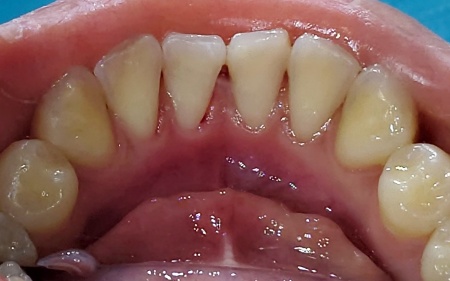

18歳女性 下前歯の裏側に付着した歯石を保険診療内のクリーニングで除去した症例

- 歯石除去

- クリーニング

- 予防歯科

- 治療期間の目安 -

- 治療回数の目安 1回

- 治療費総額の目安 保険診療内

治療のリスク

・病状、症状、患者様のお口の環境によって、複数回にわたる施術が必要となる場合があります ・治療が終わった後も、十分なセルフケアが必要です ・正しいブラッシングやメンテナンスを行わない場合、歯石の付着や虫歯が生じる可能性があります...

by.エスペレ歯科・ホープデンタルクリニック